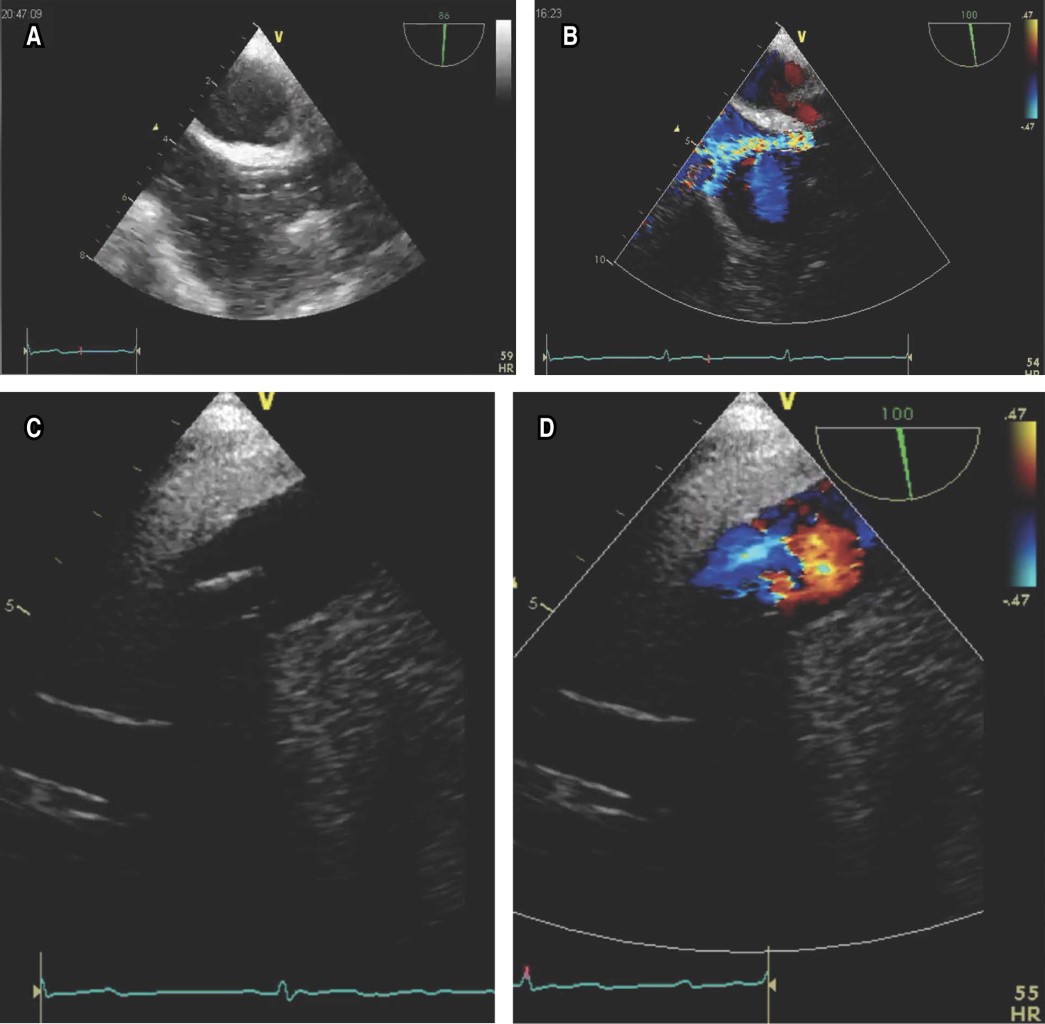

As the first step of the flowchart (Figure 1), all personnel must have adequate PPE and protect the TEE probe (Figure 2A). After intravenous sedation, the TEE probe is inserted, being the projection selected to guide the procedure the mid esophageal bicaval 90-110 degree view (Figure 2B), where we can guide in real time the correct positioning of the return (jugular) cannula (Figure 3A), which should be placed in the mid portion of the right atrium in the direction of the tricuspid valve. Adequate flow can be assessed by color Doppler (Figure 3B). The TEE probe with the same degree of angulation is advanced distally toward the esophagus to observe the inferior vena cava and the extraction cannula (femoral) which should be separated 8 to 10 cm from the return cannula (Figure 3C and D); this limits suction and recirculation phenomena.